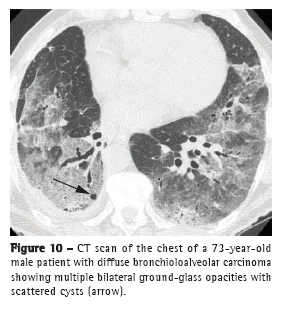

Diffuse patternThe diffuse form of BAC represents a multifocal origin, endobronchial dissemination, hematogenous metastases, or any combination of these patterns. Consolidation, nodules (Figure 9), ground-glass opacities, air bronchograms, and cysts (Figure 10), as well as peripheral distribution and distribution in the lower lobes, characterize this pattern.(20) Satellite lesions can be seen in BAC and in pneumonia.(18)